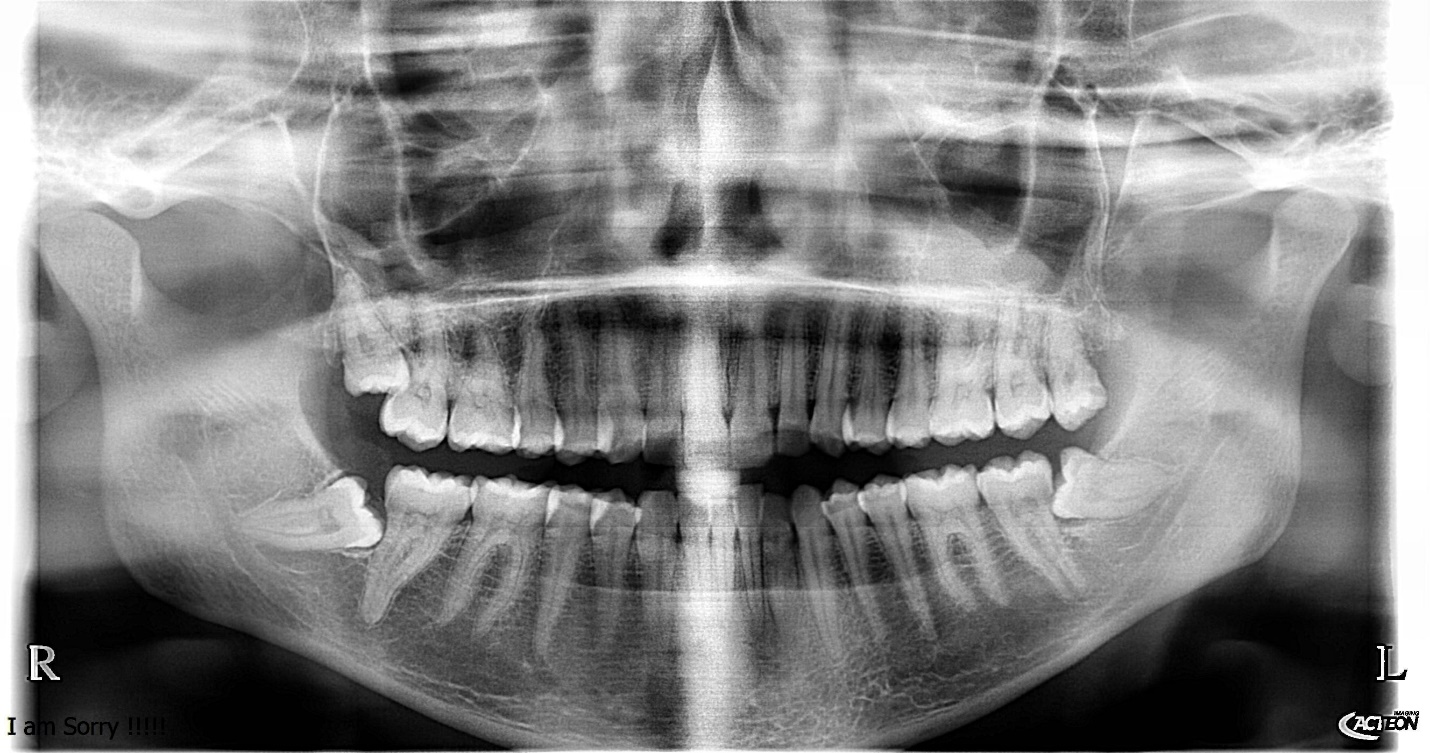

Figure 5. This panoramic showed all signs of a high risk of nerve injury (Darkening the roots. Diversion of the canal, interruption of the canal cortical)